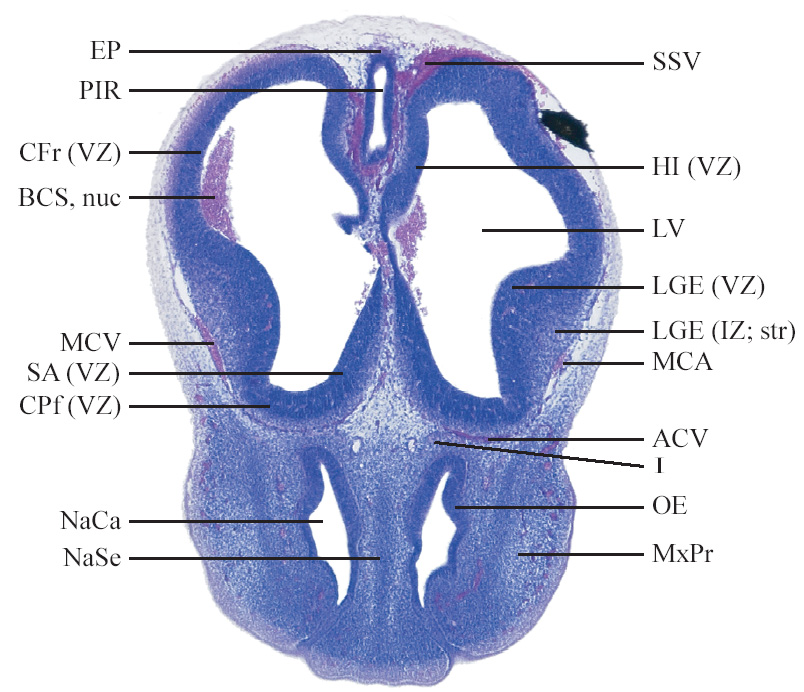

C57BL/6J GD12 Mouse Brain Atlas

Slides from U. Schambra, coronal cuts with slides at every 5th section, with a hematoxylin and eosin (H & E) stain

Currently on section 50.